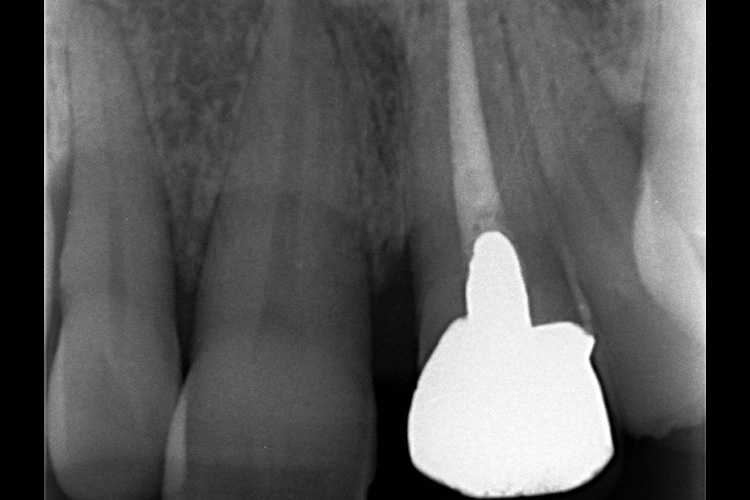

実際の実施例1

この患者様は、口腔内全体において重度の歯周病が生じており、歯磨き指導、クリーニング、Flap手術等を行ったが、歯周ポケットが深すぎるため、ブルーラジカル適用症例と診断し、施術を行いました。

(実施前)

施術前のレントゲンと口腔内写真です。施術前にプラークの除去を行ってから、施術します。